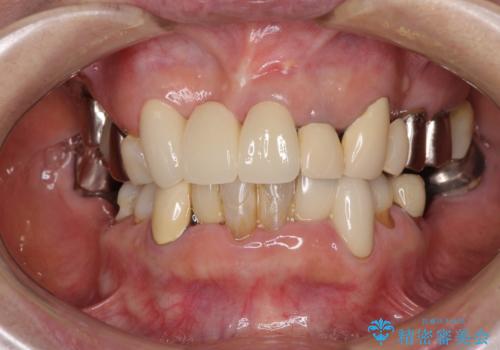

仮歯に置き換えた時点で見た目が大きく改善され、人目を気にすることがなくなりました。

オールセラミッククラウンは、仮歯以上に快適な舌触りや、本物の歯のような外観となり、患者様には大変満足していただけました。